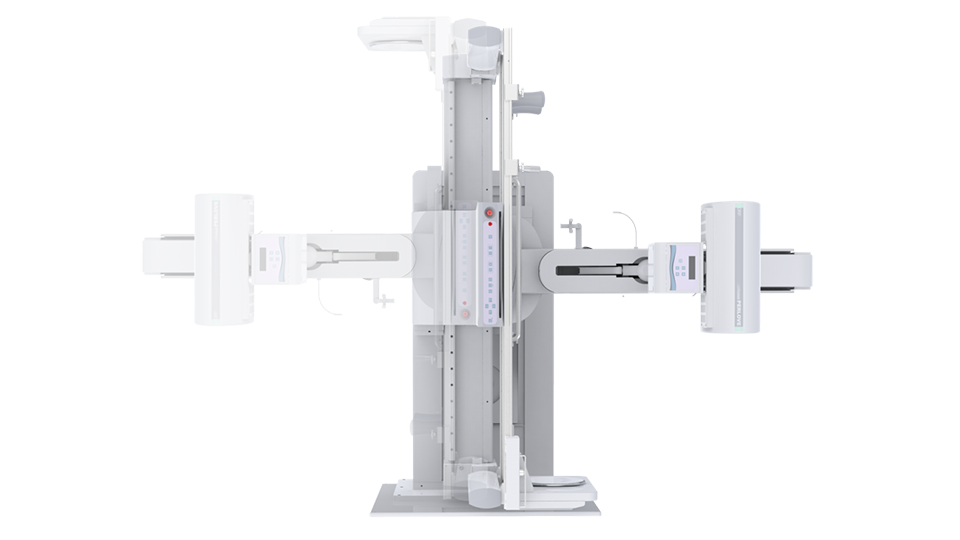

● 独特实用的床面升降功能,有利于DR摄影及行动不便的患者上下床;

● 床面可降至与病床平行高度,既方便医护人员平移患者,又避免对患者的二次伤害;

● 对于医生的近台操作也更方便,不同身高的医生可根据需要调节床体高度,更利于医生开展相关近台手术。

球管倾斜摄影角度-45°~45°,满足临床各部位各角度的摄影需求。如:髌骨轴位、颈椎正位、骶尾椎、鼻窦瓦氏位、梅氏位等部位检查。

拉伸自如:SID电动拉伸,最长可延伸至1.8米,满足放射科室各种拍片距离的需求。如:GBZ 70-2015职业性尘肺病的诊断标准中对胸片拍片距离1.8米的要求。

点片装置移动范围大,无需患者移动就能完成全身各部位的检查;

床面横向移动,轻松实现机动人不动。